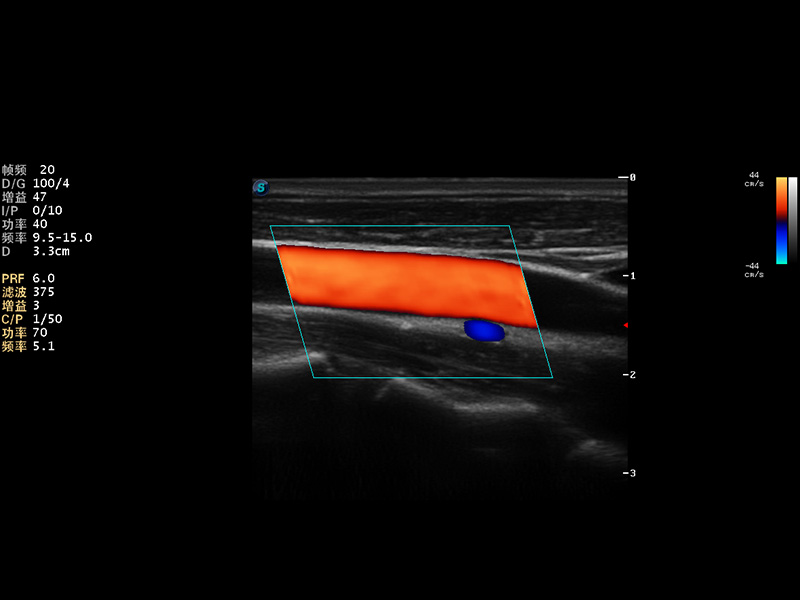

S9便携式彩色多普勒超声诊断仪是云顶集团官网研发的高端便携彩超设备,外观设计新颖、产品性能卓越。S9在便携超声领域采用了突破传统的触摸屏交互设计,并以先进的软件硬件技术和设计理念,为您带来清晰的图像质量、稳定的工作性能和便捷的操作体验。

AutoC智能血流追踪